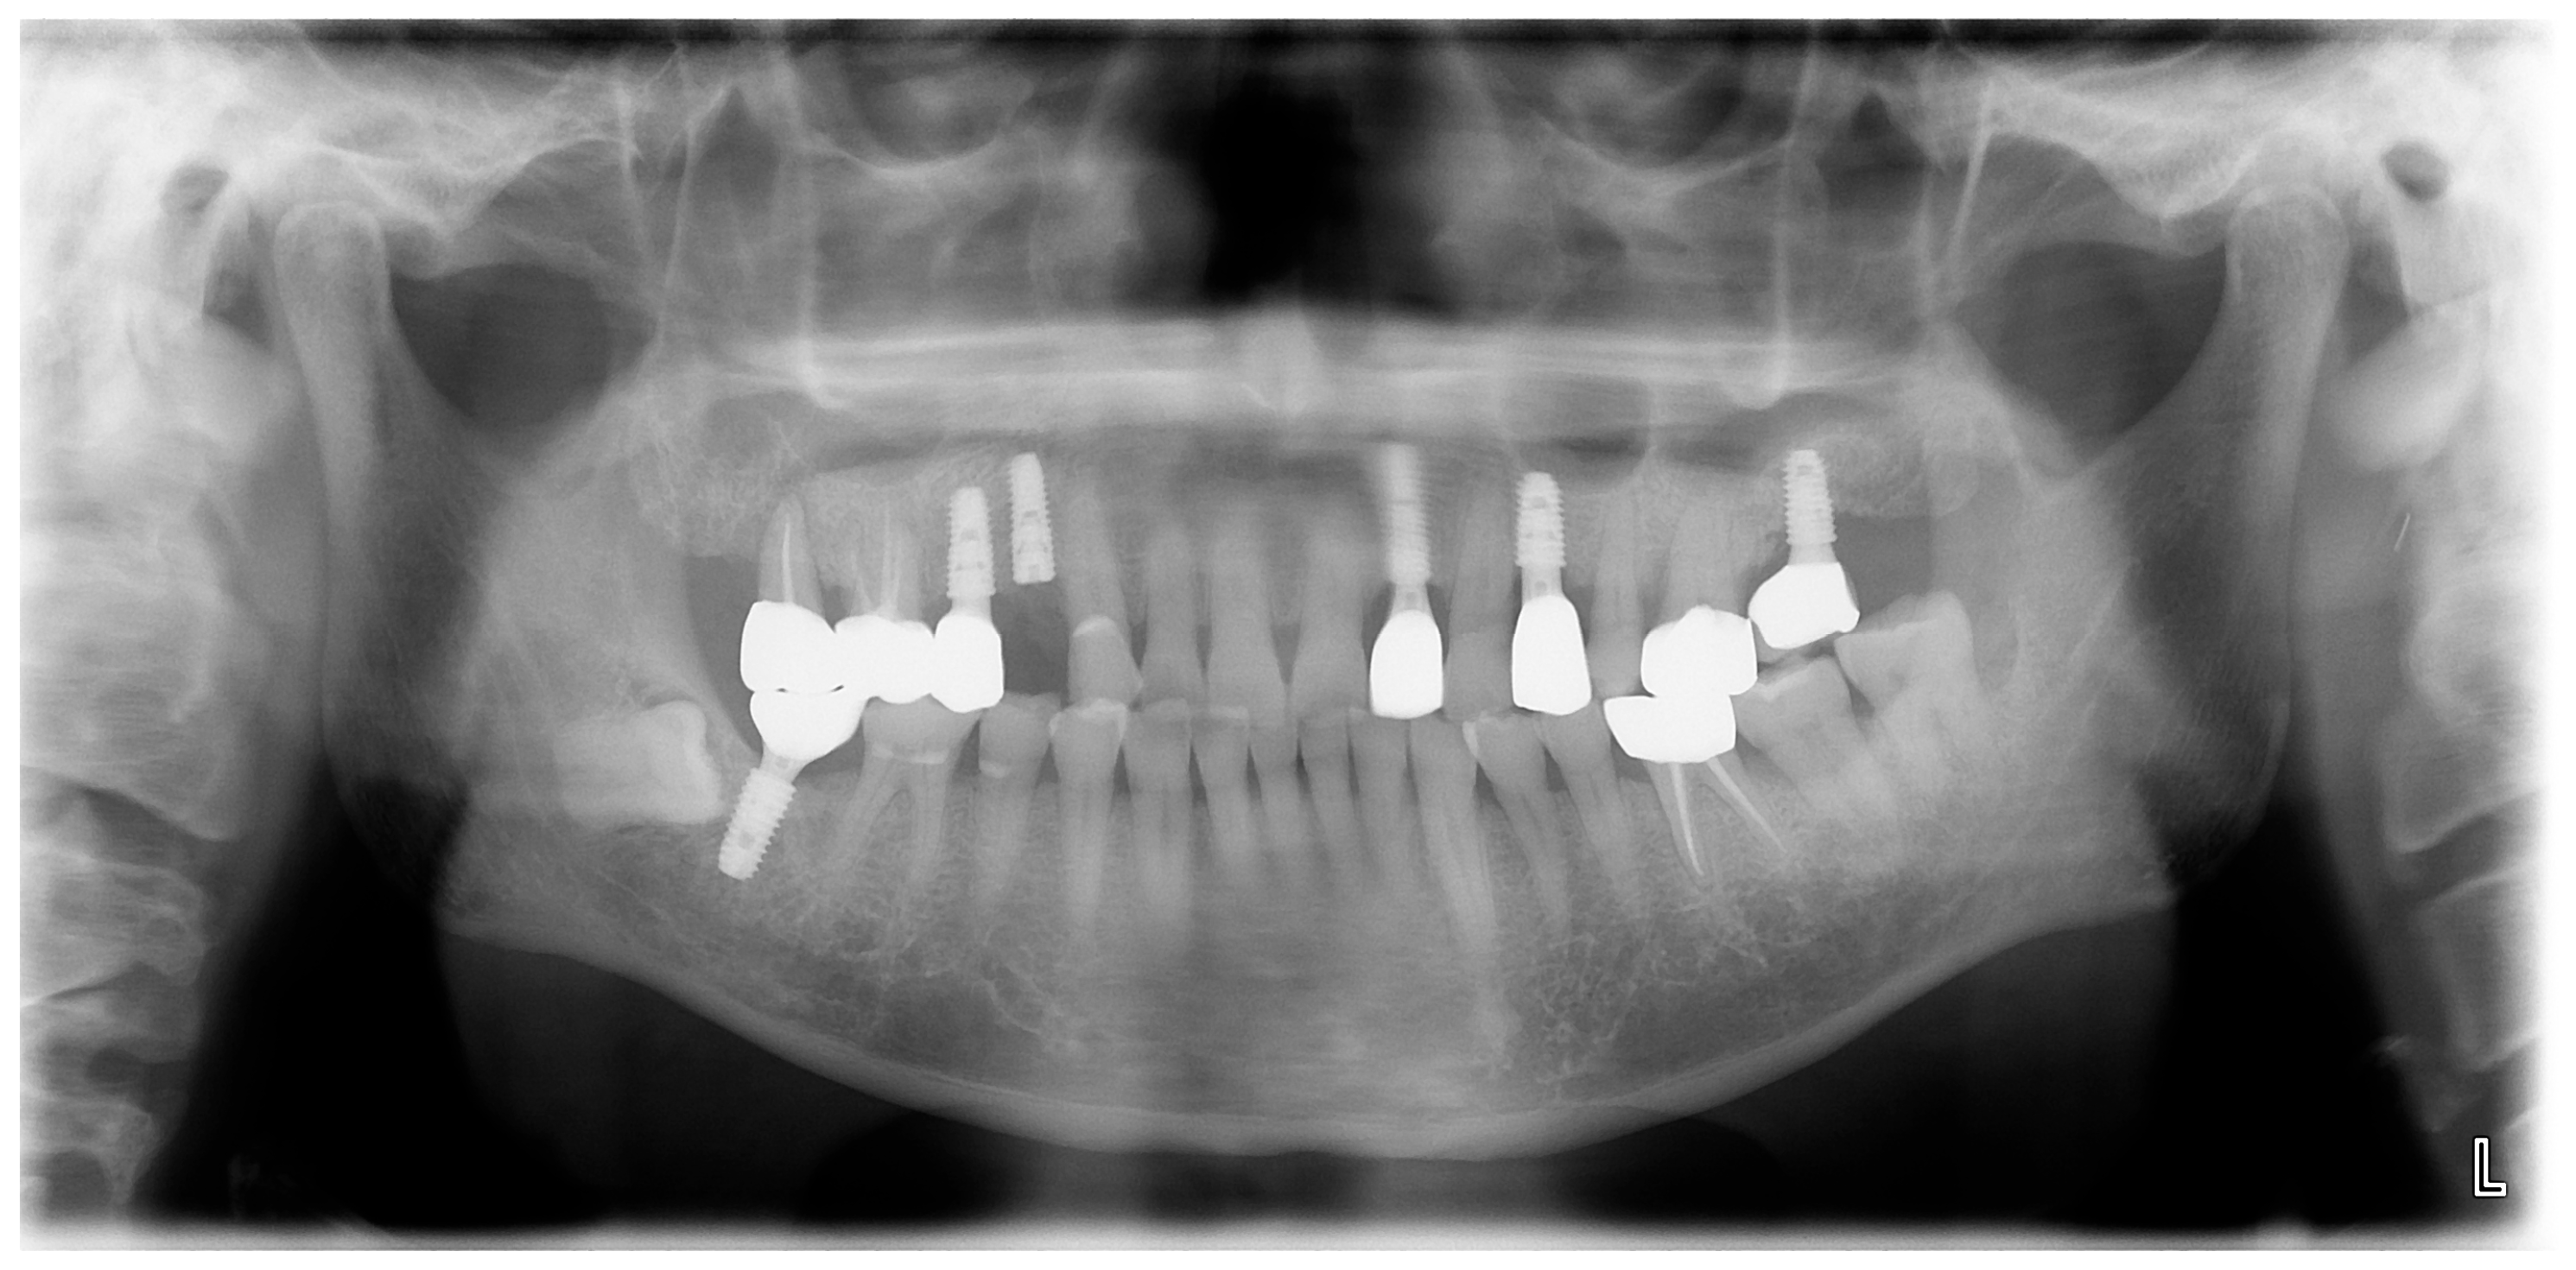

A 69-year-old male patient presenting with severe toothache 10 days before admission and melena 3 days before admission was admitted to the Infectious Disease Department of Kyung Hee University Hospital in the Republic of Korea in March 2025. The patient reported worsening toothache in the right upper gingiva with right facial swelling that began 5 days after a dental implant surgery at the upper right first premolar. Subsequently, the patient underwent incision and drainage at a local dental clinic one day before admission because of periodontitis that had spread to the facial area, as confirmed through the patient’s medical history. The patient had diabetes and was taking hypoglycemic agents. He had undergone coronary artery bypass grafting (CABG) for myocardial infarction 13 years previously. Additionally, he had undergone a prostatectomy for prostate cancer 2 years ago. He had been continuously taking clopidogrel (an antiplatelet agent) since undergoing CABG. The right buccal area of the face was swollen. Dental examination revealed a space abscess around the upper right first premolar (Figure 1). Panoramic dental X-ray showed that the implant fixture was placed in the alveolar bone of the upper right first premolar, and the external part has been removed (Figure 2). The implant fixture at the upper right first premolar was removed and irrigation and drainage were performed at the upper right first premolar and the vestibular area of the upper right second incisor, canine, and first premolar. The initial vital signs were blood pressure, 124/73 mmHg; pulse rate, 87 beats/min; respiratory rate, 20 breaths/min; temperature, 36.5 °C, oxygen saturation level, 98% on room air. Laboratory examination revealed a white blood cell (WBC) count of 6.23 × 109/L (83.0% neutrophils) and a C-reactive protein (CRP) level of 417.0 nmol/L. The aspartate aminotransferase, alanine aminotransferase, and alkaline phosphatase levels were 46, 57, and 97 IU/L, respectively. The serum creatinine level was 1.08 mg/dL and the BUN was 40 mg/dL. The serum sodium level was 129 mEq/L. Plasma level of glycated hemoglobin was 13.5%. Chest computed tomography revealed a mass-like lesion in the left lung with multiple small nodules in both lungs. Two sets of blood cultures were performed on the day of admission using BD Bactec Plus Aerobic/F and BD Bactec Plus Anaerobic/F bottles and a Bactec FX Instrument (Becton Dickinson, Sparks, MD, USA). The patient underwent esophagogastroscopy, which revealed active bleeding from multiple duodenal ulcers and subsequently received hemostatic treatment. A gastrointestinal bleeding dynamic computed tomography (CT) scan showed a liver abscess at S2/3 (3.1 cm) (Figure 3a) with focal septic thromboembolism in the left hepatic vein (Figure 3b). Chest CT revealed mass-like consolidation and air densities in the left upper and lower lobes, along with multiple irregular nodules with ground-glass opacities in both lungs (Figure 3c,d).

Figure 2. Initial panoramic dental X-ray. The implant fixture is placed in the alveolar bone of the upper right first premolar, and the external part has been removed.